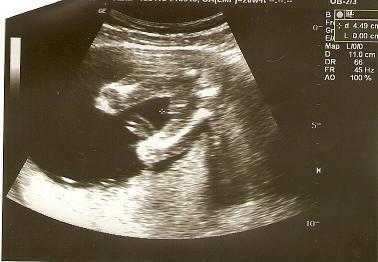

ja widzę chłopca , ale nie jestem pewna ;-)Zobacz załącznik 236421Dziewczyny a jak sądzicie jaka to płeć, lekarz nie był do końca pewny...Zobacz załącznik 236420

Zobacz załącznik 236421Dziewczyny a jak sądzicie jaka to płeć, lekarz nie był do końca pewny...Zobacz załącznik 236420

hehe, a u nas mniej wiecej tak wyglądała dziewczynka, wiec nie dziwie sie, ze lekarz nie byl pewny![]()